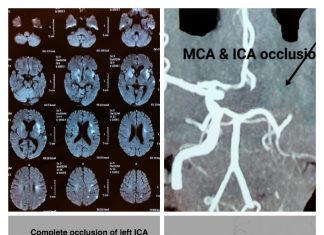

Mechanical thrombectomy after 16 hours in acute ischemic stroke at Wockhardt...

Mr. DS, was happily attending his son's marriage in his village about 350 Kms from Nagpur when he developed acute onset of right hemiparesis...